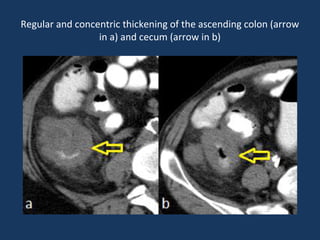

Regular and concentric thickening of the ascending colon (arrow

in a) and cecum (arrow in b)

Regular and concentricthickening of the ascending colon (arrow in a) and cecum (arrow in b)